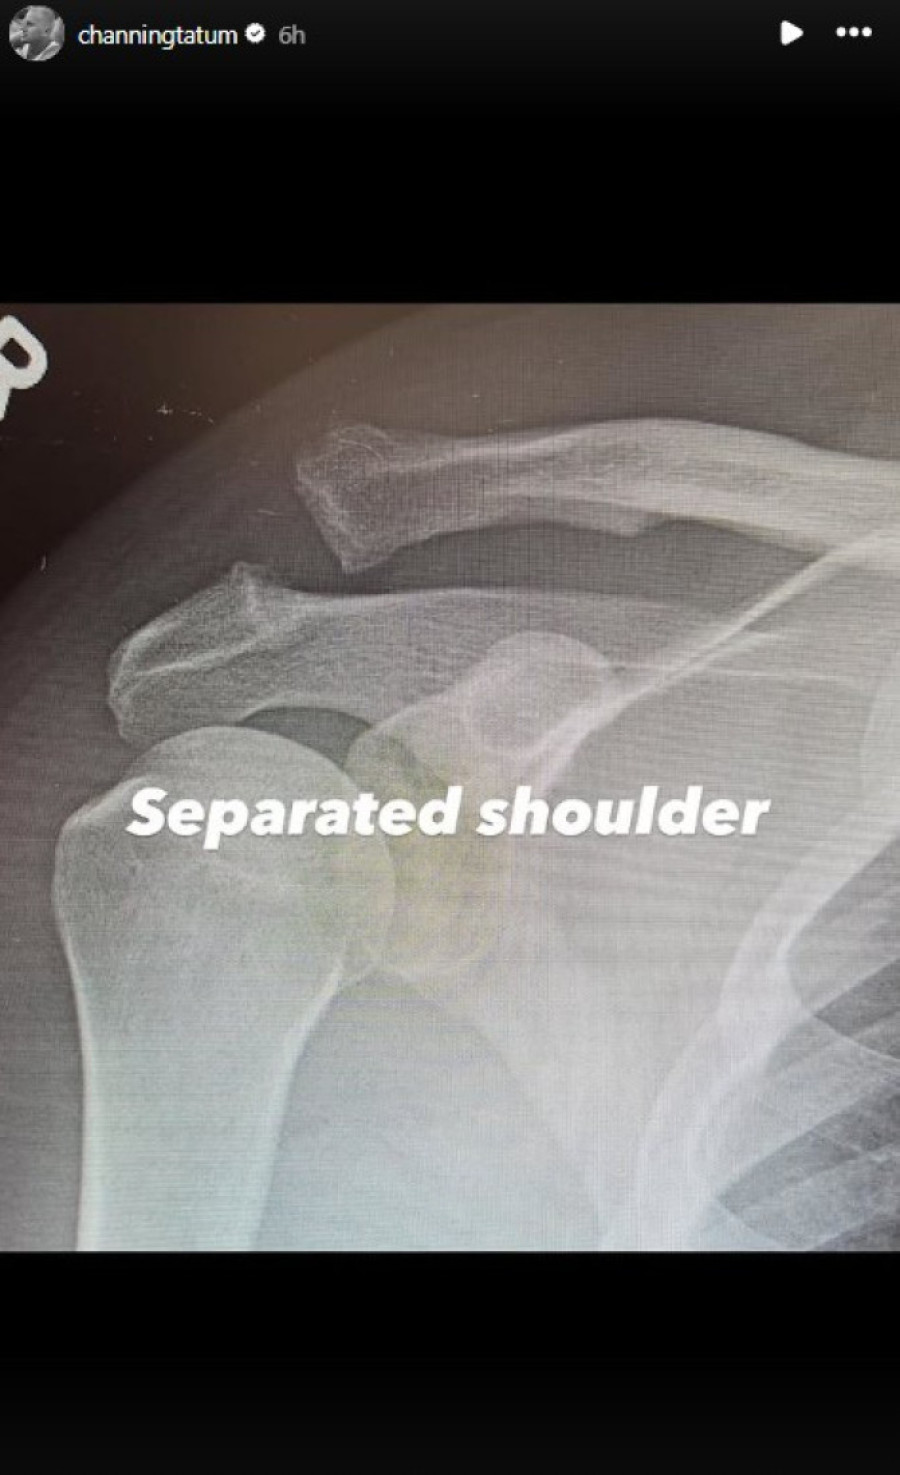

Glumac Čening Tejtum zabrinuo je brojne fanove oglasivši se na društvenim mrežama iz bolničke postelje. Kako je istakao, morao je na operaciju razdvojenog ramena, zbog čega je i hospitalizovan.

Šta se tačno dogodilo, pa je došlo do zahvata - nije otkrivao.

Čening je, podsetimo, jedan od glumaca koji sam izvodi gotovo sve svoje "stantove". Iz tog razloga - i sklon je povredama. Prošlog septembra, na primer, povredio se na snimanju "Avengers: Doomsday-a"; pojavivši se potom na jednom intervjuu bilo je jasno da šepa, a dubler ga je već bio odmenio u nekim scenama. On se, s druge strane, spremao da krene na fizikalnu terapiju.